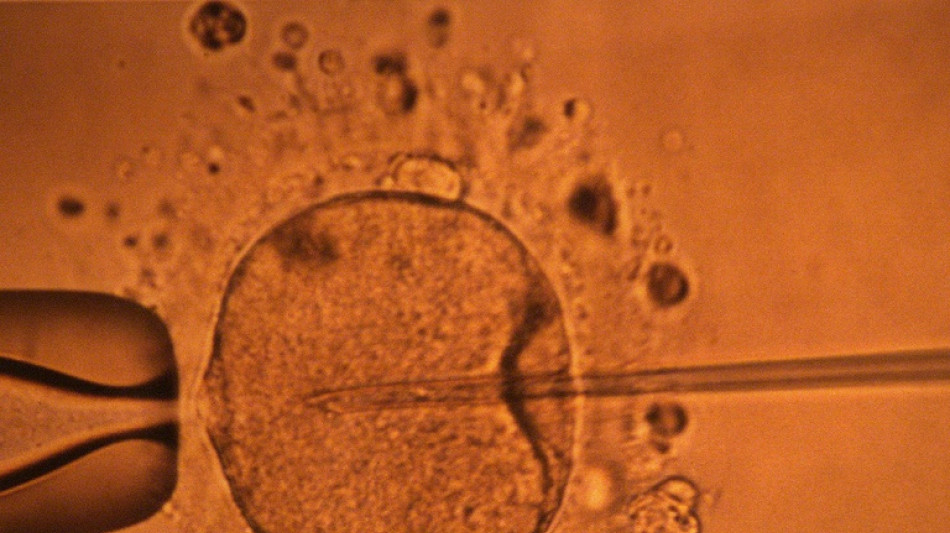

Une étude appuie l'hypothèse d'un déclin mondial de la concentration en spermatozoïdes / Photo: MARCEL MOCHET - AFP/Archives

La concentration en spermatozoïdes, l'un des facteurs de la fertilité masculine, a nettement baissé à travers toute la planète au cours des dernières décennies, avance une vaste étude publiée mardi.

"La concentration en spermatozoïdes a sensiblement diminué entre 1973 et 2018", résument les auteurs de ce travail, paru dans la revue Human Reproduction Update et réalisé en compilant une quarantaine d'études préalables.